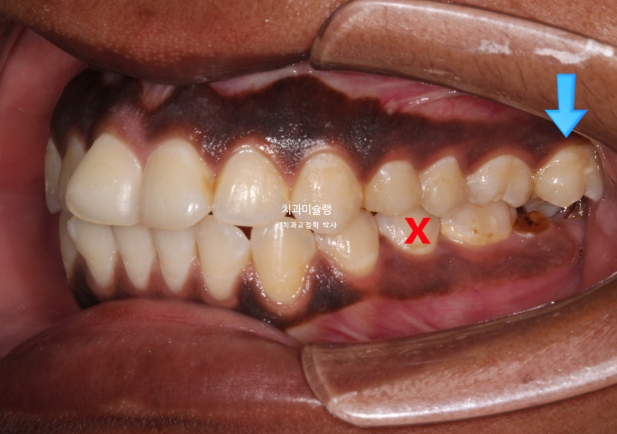

In the mandible, a molar was in a similar condition, with only the root remaining.

On the opposite side, there was a tooth that had undergone root canal treatment and had been temporarily restored. We decided to extract this tooth.

For the missing mandibular molar, ideally, the wisdom tooth could be moved forward to replace it. However, the wisdom tooth already showed root inflammation and was not in a healthy condition. Therefore, we decided to extract the wisdom tooth and proceed with orthodontic treatment, followed by implant placement in the molar region.

For the mandibular arch, we decided to extract the second premolar affected by dental caries.

In the area of the missing mandibular molar, the site had been left untreated for a long period. As a result, the opposing tooth (indicated by the blue arrow) had supra-erupted.

For proper implant placement, this opposing tooth needs to be intruded through orthodontic treatment.